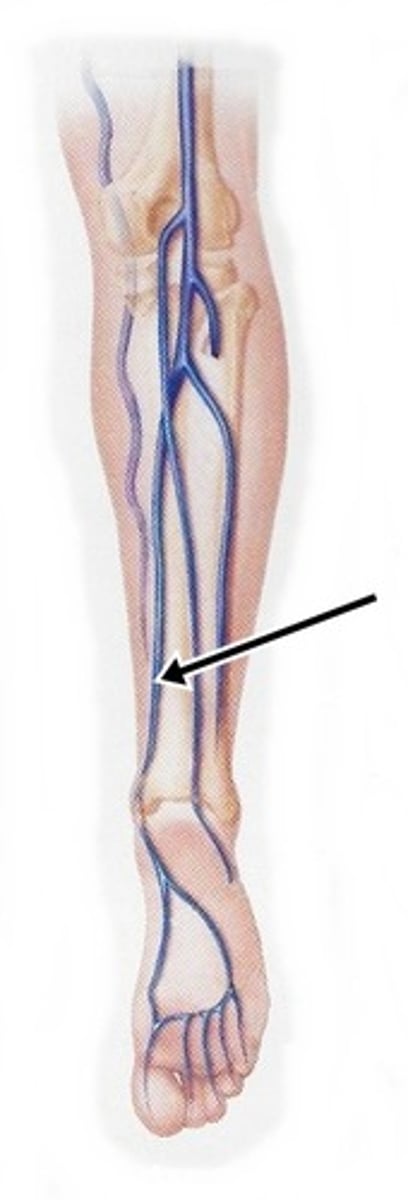

anterior tibial artery

serves the muscles in the anterior compartment of the leg

posterior tibial artery

serves the muscles in the posteromedial part of the leg

saphenous vein

longest vein in the body

popliteal vein

anterior tibial vein

posterior tibial vein